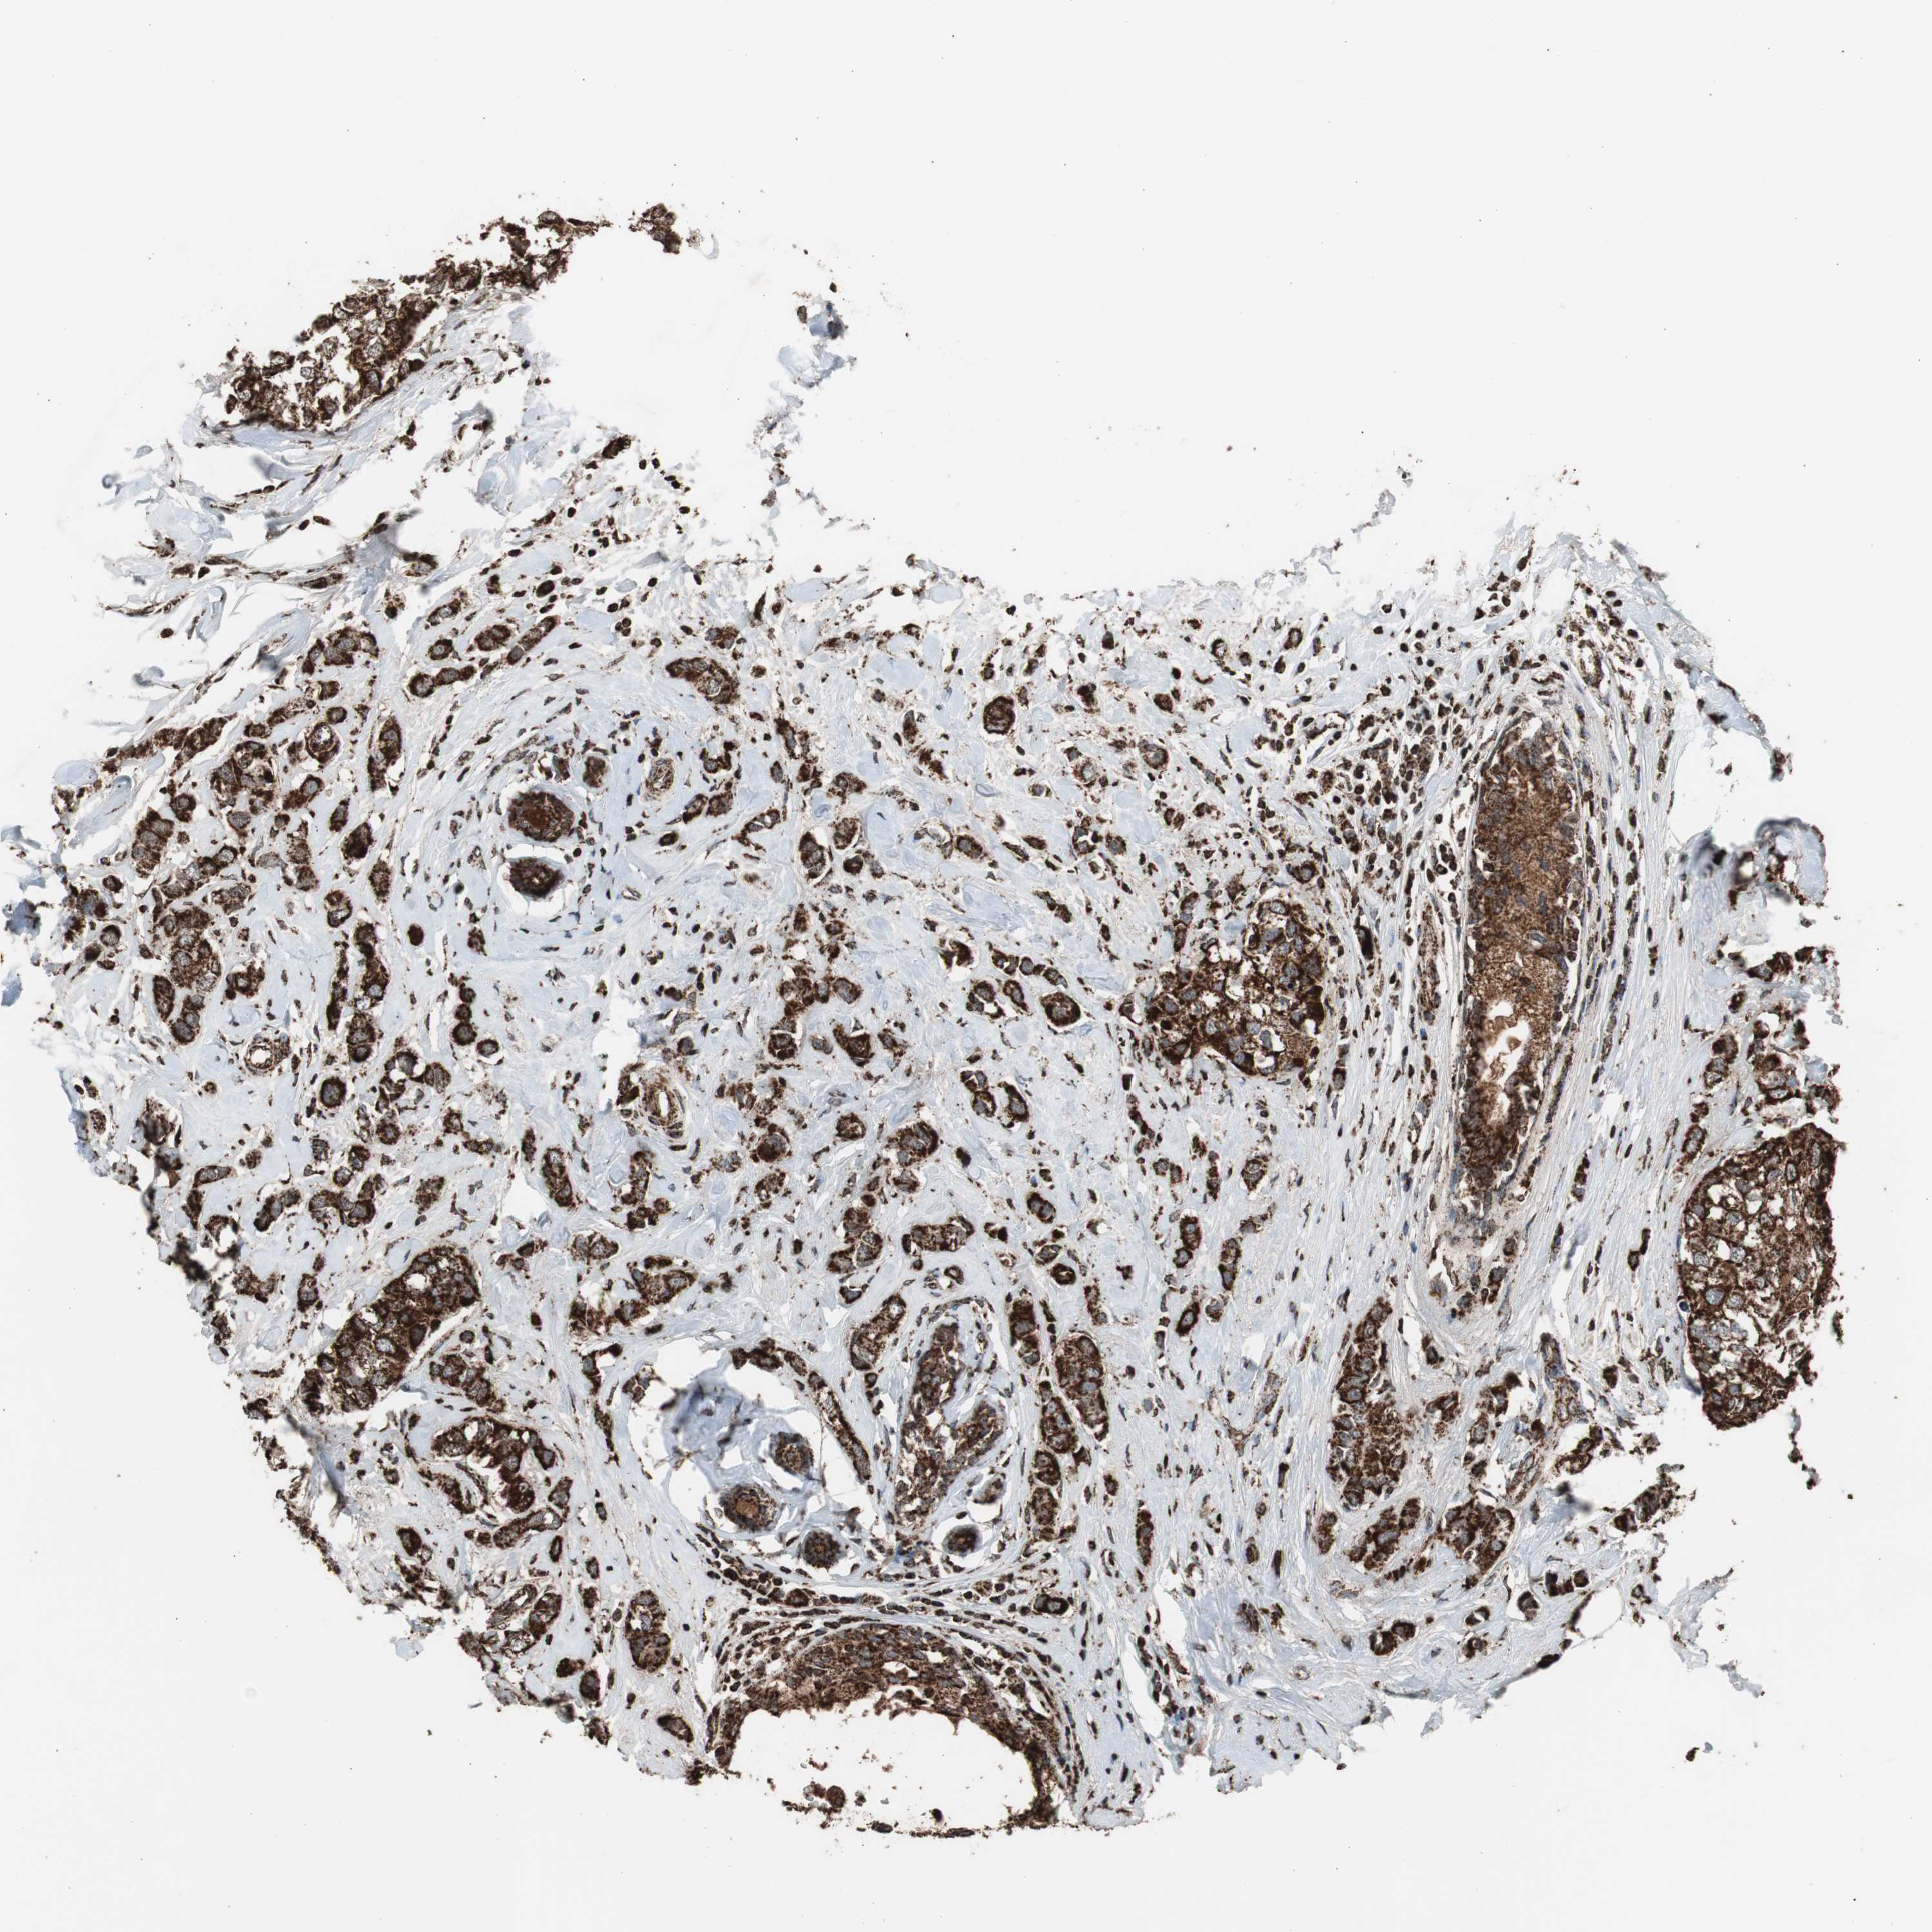

CANCER BREAST CANCER Show tissue menu

BRCA TCGA BRCA VALIDATION PROTEIN EXPRESSION